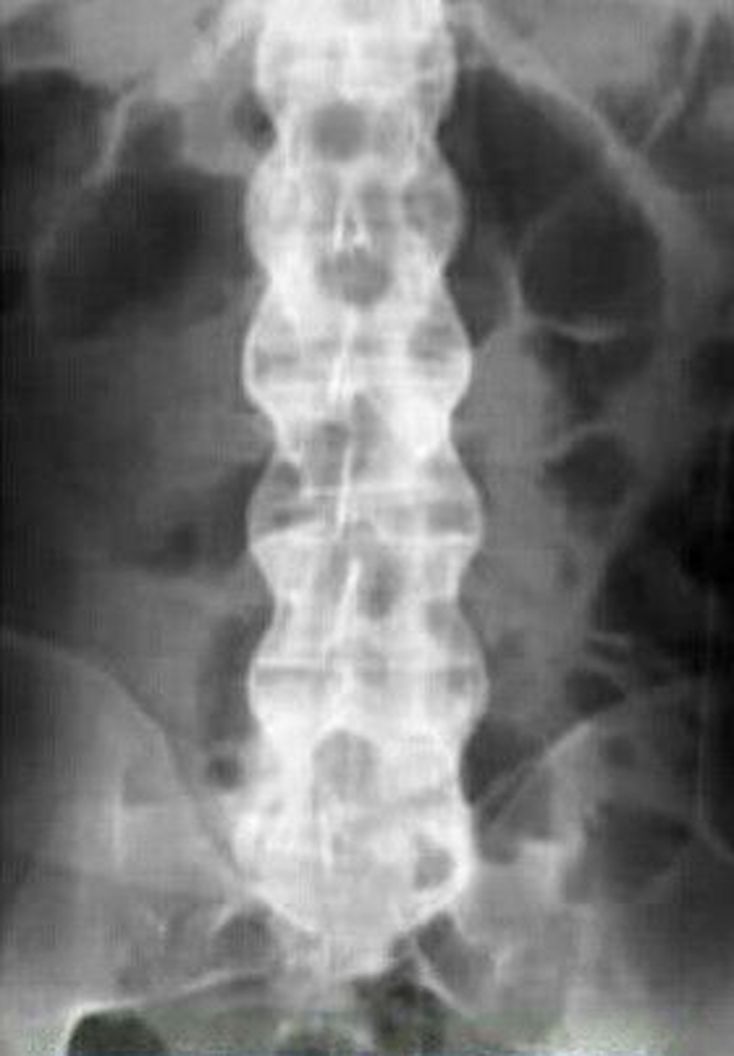

Ankylosingspondylitis

Bamboo Spine